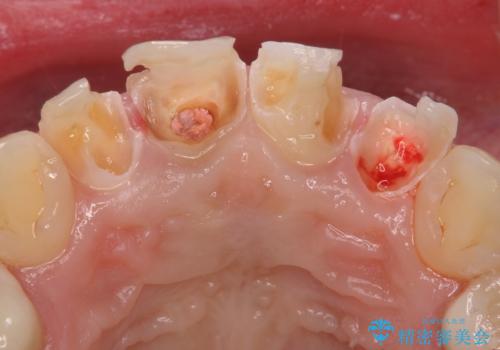

虫歯だらけの前歯をセラミック治療

- 子供の頃にジュースが原因で虫歯が多発し、レジン修復をしていたが見た目の改善を希望され来院されました。

レジン充填・虫歯を丁寧に全て除去したのちジルコニアセラミックを用いた前歯の審美改善を計画します。